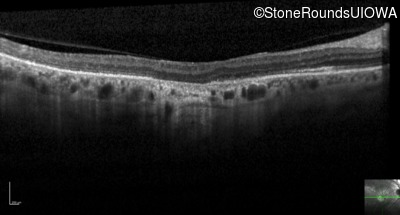

Optical Coherence Tomography - Left - 20/63

Exemplar / OCT Stack

OCT Stack